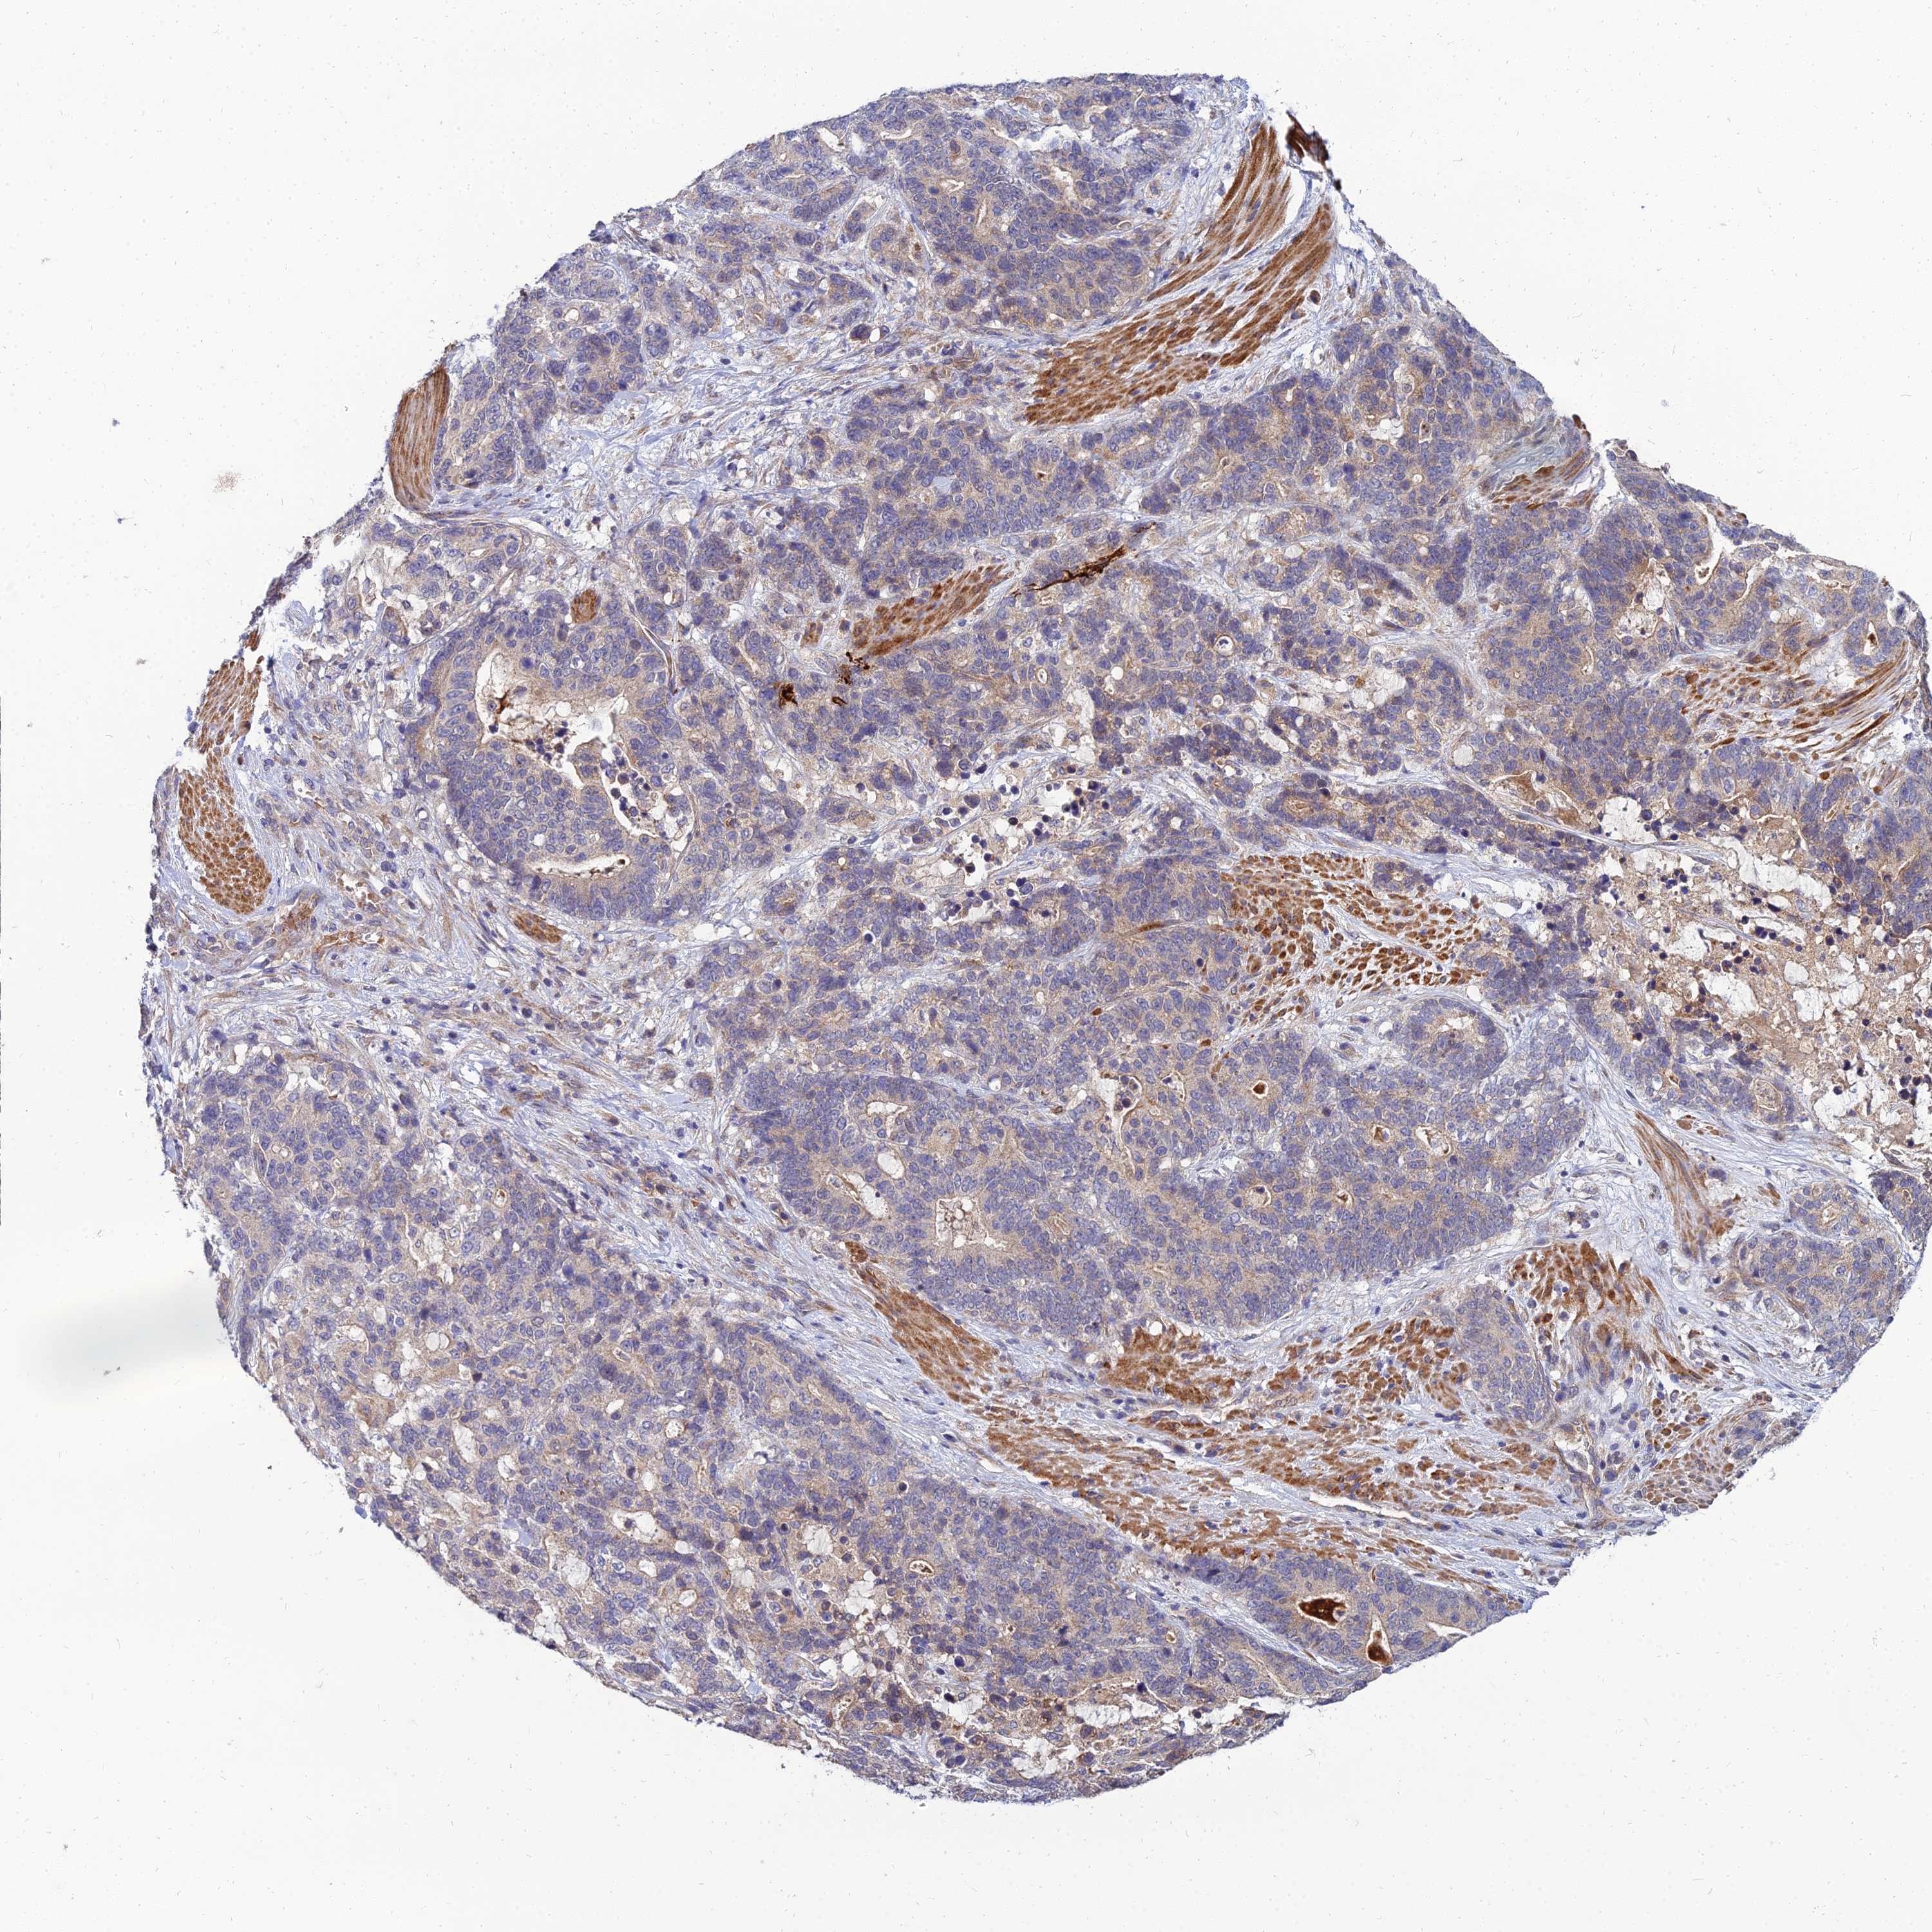

STOMACH CANCER - Protein expressioni

A mouse-over function shows sample information and annotation data. Click on an image to view it in a full screen mode. Samples can be filtered based on level of antibody staining by selecting one or several of the following categories: high, medium, low and not detected. The assay and annotation is described here.

Note that samples used for immunohistochemistry by the Human Protein Atlas do not correspond to samples in the TCGA dataset.

Antibody stainingi

Antibody staining in the annotated cell types in the current human tissue is reported as not detected, low, medium, or high, based on conventional immunohistochemistry profiling in selected tissues. This score is based on the combination of the staining intensity and fraction of stained cells.

Each image is clickable and will lead to virtual microscopy that enables deeper exploration of all samples and also displays staining intensity scores, fraction scores and subcellular localization as well as patient and tissue information for each sample.

Antibody HPA044572

Antibody HPA056798

Antibody CAB016733

Antibody CAB034368

Staining

High

Medium

Low

Not detected

Intensity

Strong

Moderate

Weak

Negative

Quantity

>75%

75%-25%

<25%

None

Location

Nuclear

Cytoplasmic/membranous

Cytoplasmic/membranous,nuclear

Adenocarcinoma, NOS